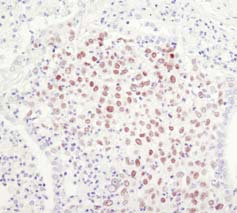

左:基于生物素的检测; 右:基于聚合物的检测

相对于基于生物素的检测而言,基于聚合物的检测的敏感性更高。

利用Sox2 (D6D9) XP® Rabbit mAb #3579 对石蜡包埋的人类肺部肿瘤进行IHC分析,采用基于生物素的检测(左)或基于聚合物的检测(SignalStain® Boost IHC Detection Reagent #8114;(右)。如图所示,基于聚合物的检测敏感度更高,染色强度更好。